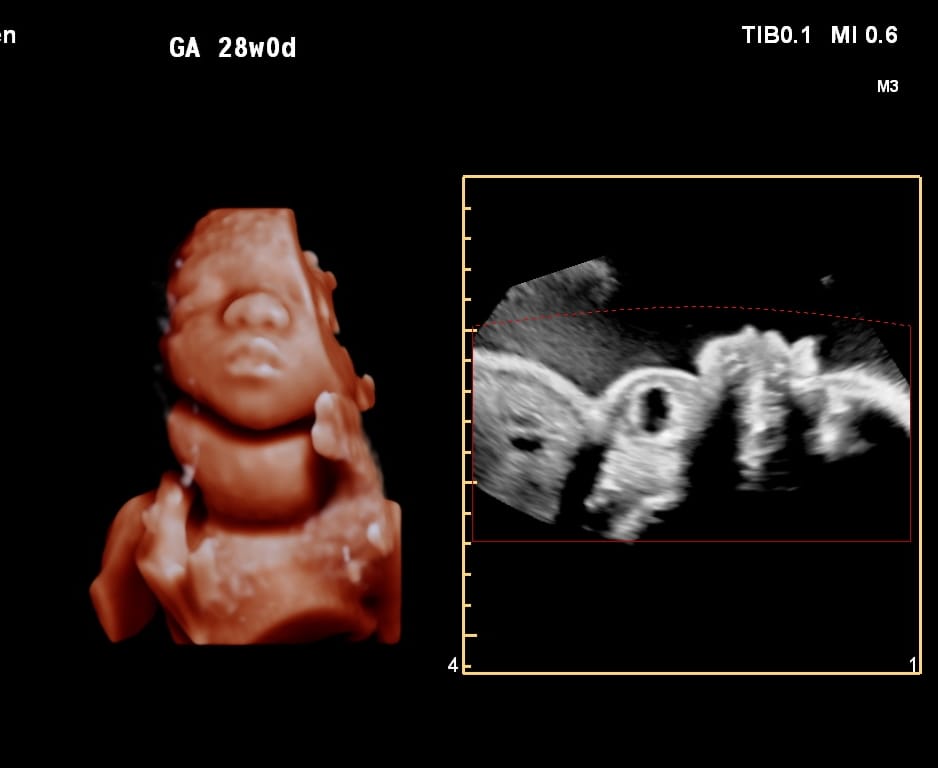

Ultrasound Services

A wide range of routine and specialized ultrasound examinations.

A wide range of routine and specialized ultrasound examinations.